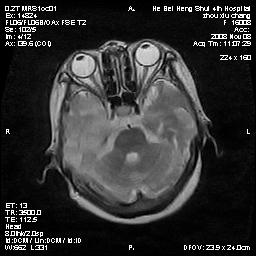

标题: MRI1883:女67岁,半年前曾患脑梗塞,治疗后好转,近3各月精

女67岁,半年前曾患脑梗塞,治疗后好转,近3各月精神恍惚。

两种可能:1,转移瘤,2,脑炎,建议增强扫描

形态及整体病灶看起来首先考虑转移瘤或淋巴瘤,但奇怪的是多个病灶周围均未见显著的水肿区,这不符合这两个肿瘤的特点,结合ct表现及患者病史有个人考虑是否有皮层下动脉硬化性脑病伴多发胶质增生可能.

不像占位性病变,考虑脱髓鞘改变

皮层下动脉硬化性脑病伴脱髓鞘改变!